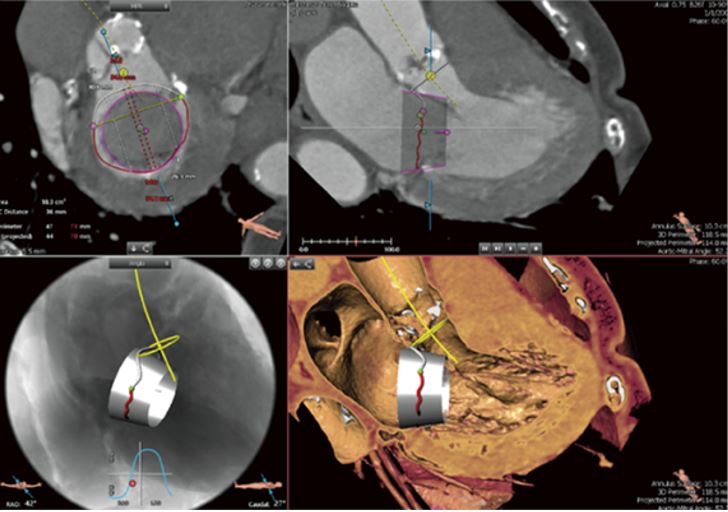

• 3mensio Structural Heart

3mensio Structural Heart полегшує передопераційне планування операцій на аортальному, мітральному клапані, коронарних процедур

CTA ПЗ планування TAVR

3mensio Structural Heart/Mitral Valve SW

ПЗ 3mensio аортального клапану